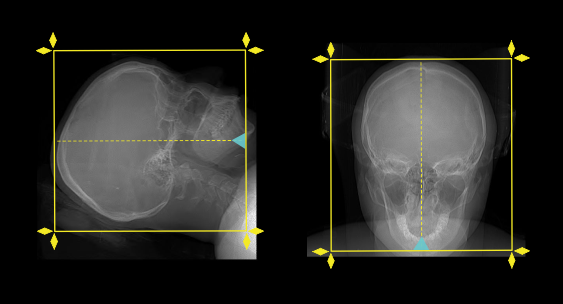

Scan planning

- Plan the scan starting point at the angle of the mandible (patient in prone and head first position).

- Plan the scan slab to cover from the skull vertex to mandible.